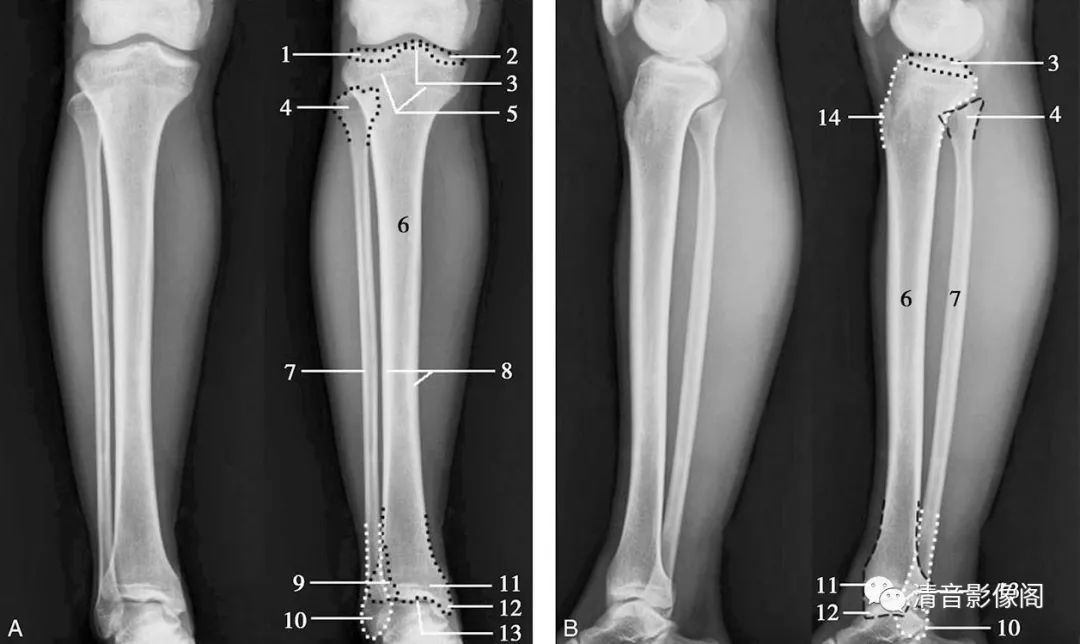

成人胫腓骨正侧位

1. 胫骨外侧髁;2. 胫骨内侧髁;3. 胫骨髁间隆起 ;4. 腓骨头 ;5. 胫骨近端骺线 ;6. 胫骨体 ;7. 腓骨体;8. 胫骨皮质骨;9. 胫骨腓骨切迹;10. 外踝;11. 胫骨远端骺线;12. 内踝;13. 踝关节面;14. 胫骨结节。